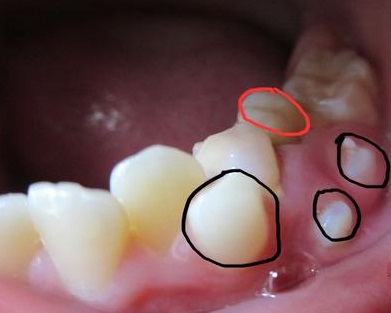

多生牙又称额外牙,是正常恒牙数量以外再多长出的牙齿,即全口牙齿除了20颗乳牙和32颗恒牙外,额外多长出的牙齿。它可能来自形成过多的牙蕾,也可能是牙胚分裂而成。多生牙可发生在颌骨的任何部位,但最常见的是"正中牙",位于上颌两颗门牙中间,常为单个,有时也会成对出现。多生牙可以萌出或者完全埋在颌骨内,而埋在颌骨内的额外牙常常影响邻牙的位置,甚至阻碍其正常萌出,进而导致牙齿排列不齐,除了影响美观外,还会成为龋病和牙周病的发病因素。

为减少多生牙对恒牙和恒牙列的影响,已萌出的多生牙应及时拔除,以有利于邻近恒牙的顺利萌出并减少恒牙的错位。对于未长出的多生牙,如果影响恒牙的发育、萌出及排列,在不损伤恒牙胚的情况下应尽可能早拔除,若不影响恒牙胚的发育和萌出,可等恒牙牙根发育完成后再拔除,拔除时手术必须仔细小心,切勿因拔除多生牙而伤及正在发育的恒牙牙根。